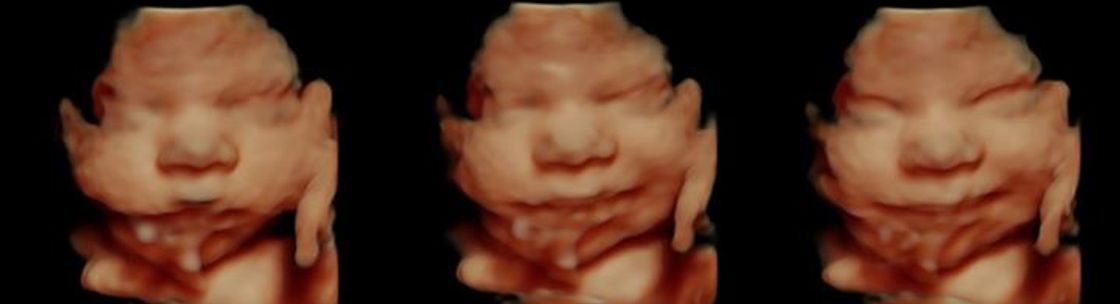

3d 4d Ultrasound Studio